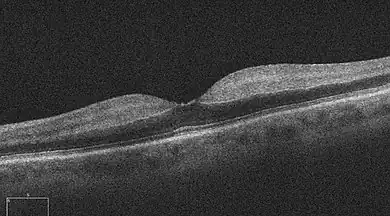

One diagnostic method for the confirmation of CRAO is Fluorescein angiography, it is used to examine the retinal artery filling time after the fluorescein dye is injected into the peripheral venous system.[2] In an eye with CRAO some branches of the retinal artery may not fill or the time it takes for the branches of the retinal artery to fill will be increased, which is visualized by the leading edge of the fluorescein moving slower than normal through the retinal artery branches to the edges of the retina.[2] Fluorescein angiography can also be used to determine the extent of the occlusion as well as classify it into one of four types non-arteritic CRAO, non-arteritic CRAO with cilioretinal artery sparing, transient non-arteritic CRAO and arteritic CRAO.[3] Optical coherence tomography (OCT) may also be used to confirm the diagnosis of CRAO.[4]